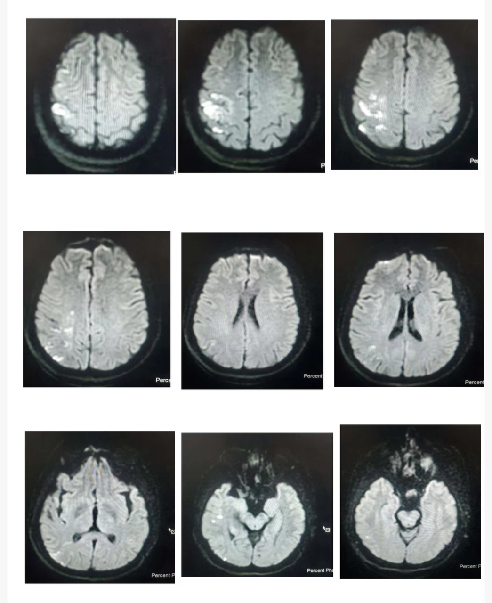

入院影像检查

急诊脑CT检查。

术后第二天磁共振。

导丝怎么扩【载药时代 球扩天下】NOVA DES®颅内药物洗脱支架在颈内动脉颅内段重度狭窄的应用两例!滕州市中心医院&山西医科大学第二医院_https://www.jmylbn.com_新闻资讯_第10张

术后第二天。

导丝怎么扩【载药时代 球扩天下】NOVA DES®颅内药物洗脱支架在颈内动脉颅内段重度狭窄的应用两例!滕州市中心医院&山西医科大学第二医院_https://www.jmylbn.com_新闻资讯_第11张

导丝怎么扩【载药时代 球扩天下】NOVA DES®颅内药物洗脱支架在颈内动脉颅内段重度狭窄的应用两例!滕州市中心医院&山西医科大学第二医院_https://www.jmylbn.com_新闻资讯_第13张

2022-10-28,DWI